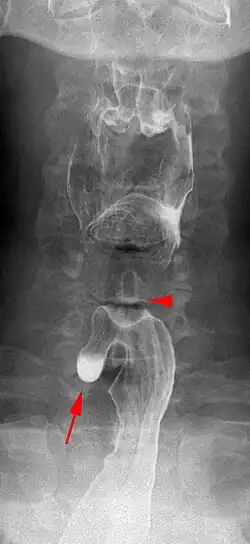

Das Killian-Jamieson-Divertikel ist wie das viel häufigere Zenker-Divertikel ein Pulsionsdivertikel am oberen Speiseröhren-Sphinkter. Es hat seinen Ursprung jedoch unmittelbar unterhalb des Sphinkters und ist somit im Gegensatz zum Zenker-Divertikel tatsächlich ein Divertikel der Speiseröhre.

Die Lokalisation nach ventrolateral unmittelbar unter dem Musculus cricopharyngeus oder nach dorsal durch das Laimer-Dreieck ergibt sich durch die anatomischen Schwachstellen hier. Mitursächlich sind Druckspitzen zwischen einzelnen Muskelpartien der obersten Anteils der Speiseröhre.

Killian-Jamieson-Divertikel erreichen selten eine Größe von mehr als 1,5 cm. Divertikelträger sind in der Regel symptomlos, was sich dadurch erklärt, dass eventuell retinierte Speisereste nicht wie beim Zenker-Divertikel nach oben in den Pharynx oder in die Luftwege gelangen können.